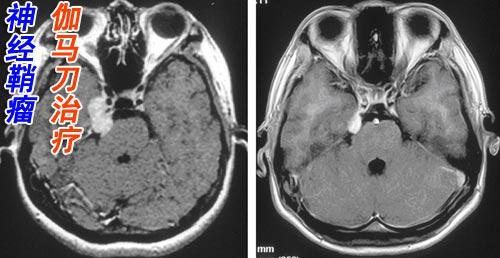

放疗只是一种局部治疗方案,只能杀灭局灶的肿瘤细胞,也就是说,只能是射线照射的部位,对于其他部位的肿瘤是没有效果的,不能杀灭身体远处的癌细胞。所以,放疗只能用于肿瘤的局部治疗,例如小的肝癌、局部直肠癌,颅内肿瘤,鼻咽癌,或者肿瘤局部复发等等。大家听说过的的X刀、伽玛刀,射波刀也属于放疗。